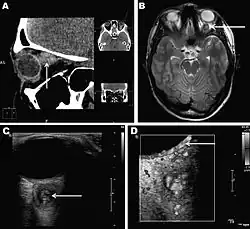

Retro-ocular nodule of a D. repens worm detected in a 20-year-old woman, Rostov-na-Donu, Russia: The cyst (arrows) is shown by computed tomography scan (A) and magnetic resonance imaging (B). Ultrasonography image (C) shows a worm-like structure inside the cyst (arrow), and color Doppler imaging (D) shows marginal vascularization of the lesion).

Infections in humans[3] usually manifest as a single subcutaneous nodule, which is caused by a macrofilaria that is trapped by the immune system. Subcutaneous migration of the worm may result in local swellings with changing localization. In addition, rare cases of organ manifestation have been reported, affecting the lung, male genitals, female breast, or the eye. The latter is found in particular during the migratory phase of the parasite. D. repens occurs more commonly in adults (aged 40–49 years). The only exception is in Sri Lanka, where children younger than nine years are most likely to be infected. The youngest individual reported was aged four months.[4]